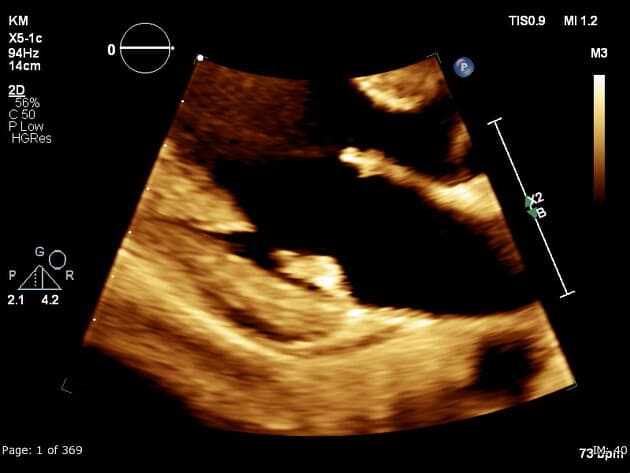

- Thông tim thất trái (left ventriculography): đoạn cơ sở của thất trái tăng động (hyperkinetic), trong khi các đoạn giữa và đỉnh thất trái giảm động (hypokinetic) với phân bố không theo vùng cấp máu của động mạch vành. Hình ảnh cuối tâm thu cho thấy dạng "nồi bắt cá mực" điển hình (classic 'octopus pot').

Bệnh cơ tim Takotsubo (Takotsubo cardiomyopathy)

- "Hình ảnh 'nồi bắt cá mực' điển hình trên thông tim thất trái là do tăng động ở các đoạn cơ sở, trong khi các đoạn giữa và đỉnh bị giảm hoặc mất động."